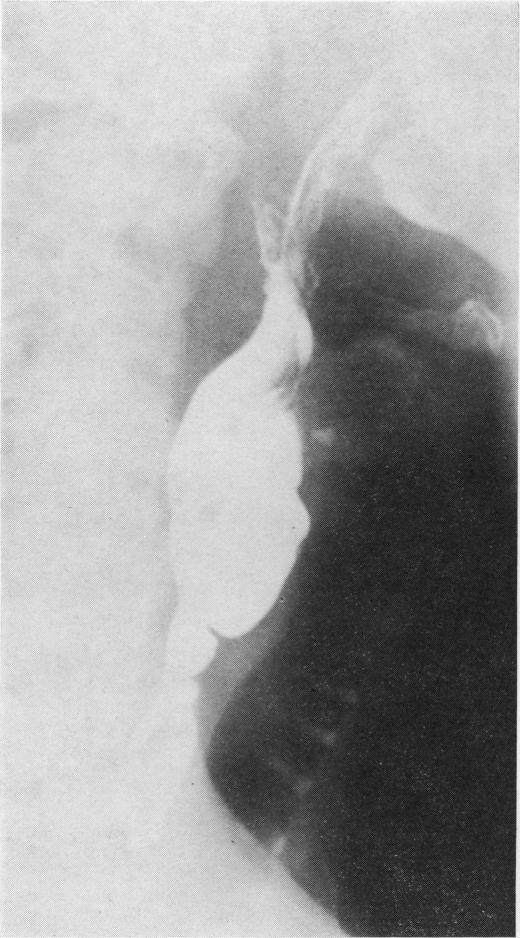

The anatomical variations of the Plummer-Vinson stricture in the cervical oesophagus. An X-ray atlas.

Ulster Med J. 1978;47 Suppl 2(Suppl 2):15-59.